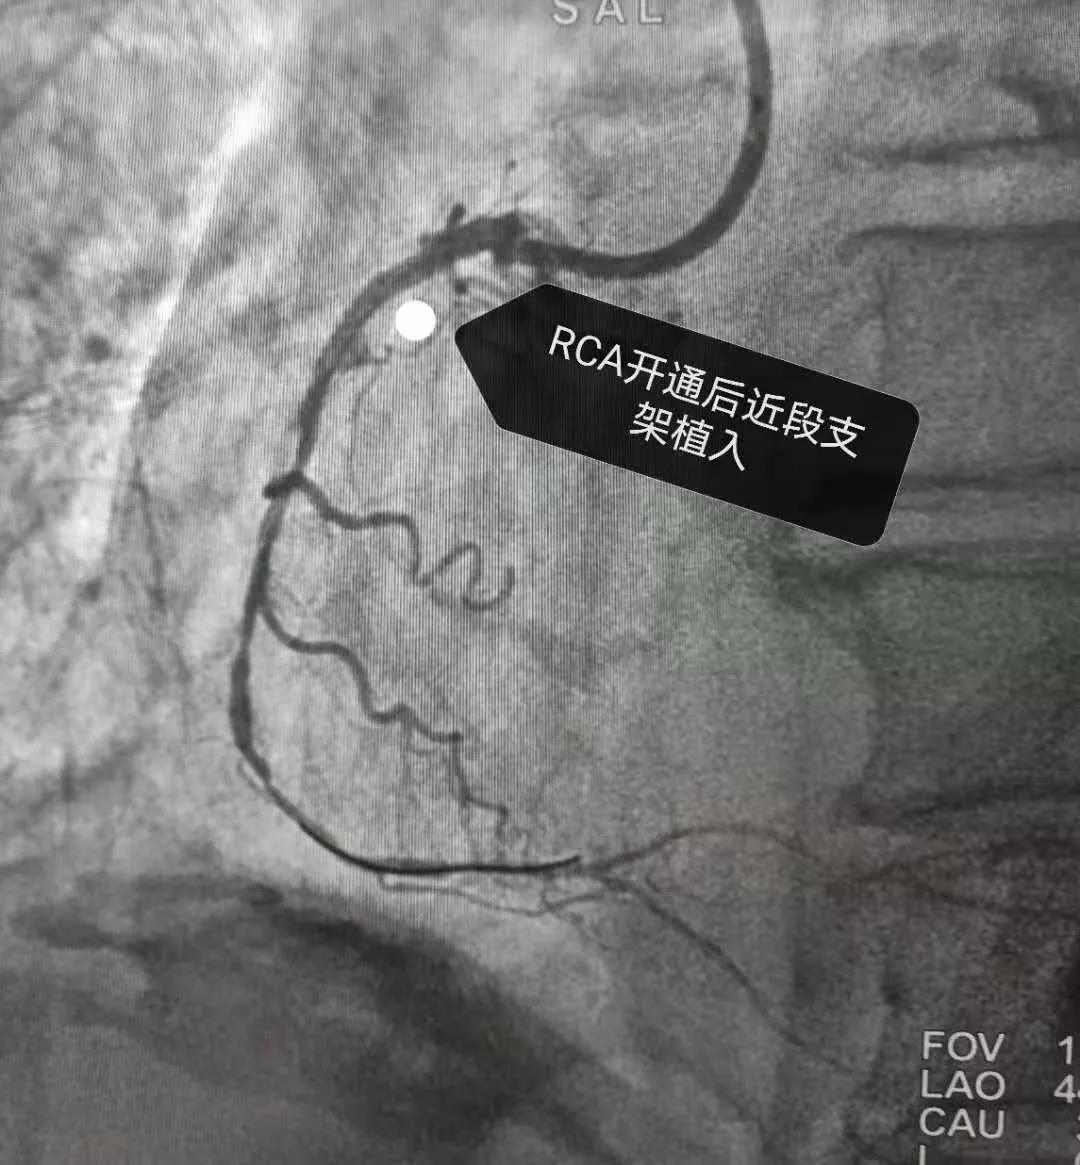

随州市中医医院成功独立完成首例对侧造影,开通右冠CTO病例!

近日,我院心血管病科丁红主任带领团队成功独立完成我院首例对侧造影,开通右冠CTO病例。所谓的对侧造影简单的说就是从右边看左边堵塞的血管或是从左边看右边堵塞的血管。CTO病变被公认为复杂病变,开通CTO病变,标志着我院冠脉介入技术水平已得到极大的提升,达到了省内先进水平;同时意味着我院心血管病科为此类患者的治疗带来了希望与福音,此项技术的独立完成,而且该项技术在随州地区很少被应用,不仅为患者节约了治疗费用,还成为我市CTO病变介入治疗技术的领军者。

老年男性患者,因典型心绞痛症状两年来我院门诊就诊,入院后心电图提示陈旧性下壁心肌梗死,心血管病科丁红主任与患者及家属沟通,告知冠脉造影+冠脉支架植入术的必要性后安排冠脉造影术检查。

右冠状动脉从近段就“截流”了

对右冠状动脉行球囊扩张及支架植入

再来看看开通前后的状态是不是一样的呀